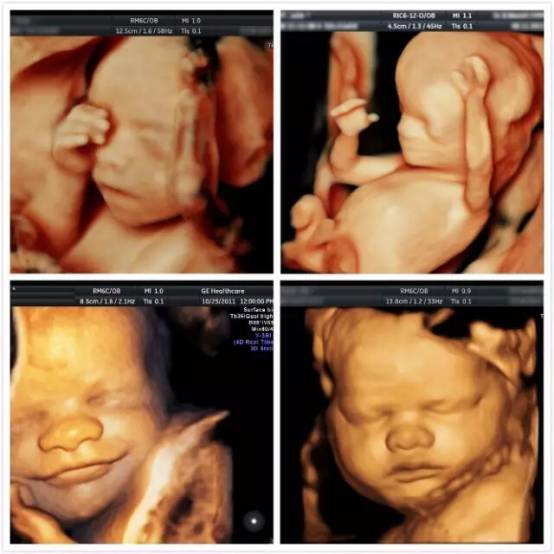

四维彩超是超声检查的一种,除了一般彩超的功能外,还可以进行胎儿头面部立体成像,可清晰地显示眼、鼻、口、下颔等状态,可协助医生直接对胎儿先天畸形进行诊断,包括表面畸形、内脏畸形和头面部畸形,能确定胎儿在子宫中的精确位置。

四维彩超与一般超声检查相比,四维彩超在超声诊断方面具有四维图像成像速度快、图像清晰、分辨率高等优势,能够多方位、多角度地观察宫内胎儿的生长发育情况,为早期诊断胎儿先天性体表畸形和先天性心脏疾病提供更为准确的依据。

四维彩超还能让准爸妈提前跟胎宝宝“见面”,看到胎儿在母体内的实时动态,如微笑、打呵欠、皱眉头、做鬼脸、吸手指、伸懒腰、吐舌头等,这些都是一般的B超无法做到的。四维彩超能动态的记录胎宝宝在母体里成长的珍贵时刻,还能制作成光盘,让宝宝拥有今生只有一次的0岁相册,留下永久的记忆。